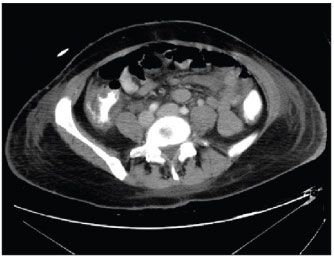

Figure 1 –A CT scan of the abdomen shows colonic wall thickening and stranding of the ascending colon.

The results of a C difficile toxin test of the stool were negative on 3 samples. The WBC count increased to 22,000/µL, with 40% bands. Abdominal and pelvic CT scans showed moderate thickening of the ascending colon with mesenteric stranding and mild thickening of the descending colon (Figure 1). Two sets of blood cultures and a superficial culture from the right thigh demonstrated growth of K oxytoca. Susceptibility testing showed piperacillin and piperacillin/tazobactam resistance. Deep tissue cultures taken the same day from the thighs were negative, and Gram stains did not show any gram-negative rods.